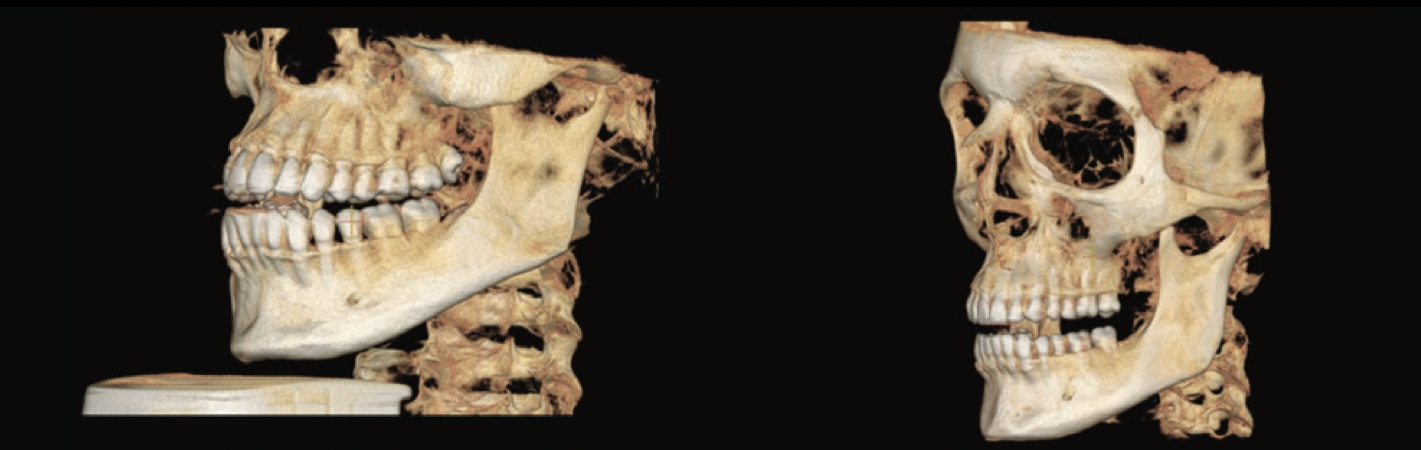

Comparativa imagen CBCT FOV 16 x 10 versus FOV 15 x 15.

A diferencia de las imágenes digitales en 2D, las imágenes 3D están construidas de voxels y no de pixels. El voxel es el elemento más pequeño del volumen de la imagen radiográfica 3D y su tamaño está dado por su altura, anchura y profundidad. En TC los voxeles son anisotrópicos, esto quiere decir que no son idénticos en todos los planos ya que su altura depende del grosor del haz de TC, es decir del grosor de corte, esto hace que en determinados planos como el sagital la precisión sea limitada ya que depende de la distancia de los cortes (gap). En cambio, en CBCT los voxeles son isotrópicos, idénticos en altura, anchura y profundidad y esto permite imágenes geométricamente más precisas en cualquier plano.